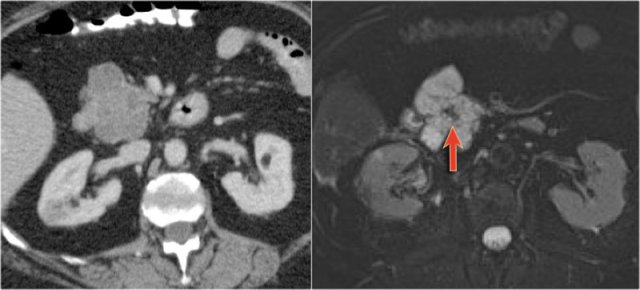

The images show a serous cystic neoplasm (SCN) on a CT.

MRI better shows the central scar.

There are cases when CT can be helpful, since it better depicts a central calcification in SCN or peripheral calcification in a mucinous cystic neoplasm (MCN).

CT images of a mucinous cystic neoplasm with septations and peripheral calcifications.